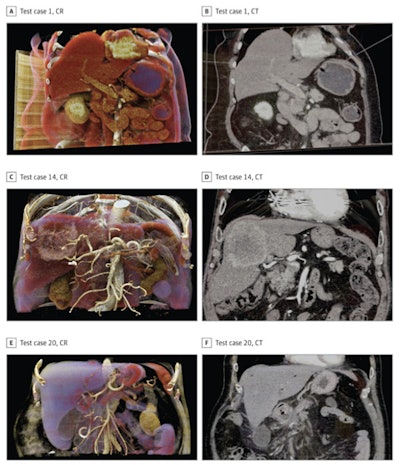

Cinematically rendered images (left column) juxtaposed with corresponding CT scans (right column) of pancreatic (A-B) and liver (C-F) anatomy. Images courtesy of Elshafei et al. Licensed under CC BY 4.0.A total of 18 resident and attending surgeons used either the conventional CT scans or cinematically rendered CT images to complete an assessment concerning essential facets of patient anatomy in the context of preoperative planning and intraoperative strategies. Those who examined the conventional CT scans first also examined the cinematically rendered images following a two-week washout period, and vice versa.